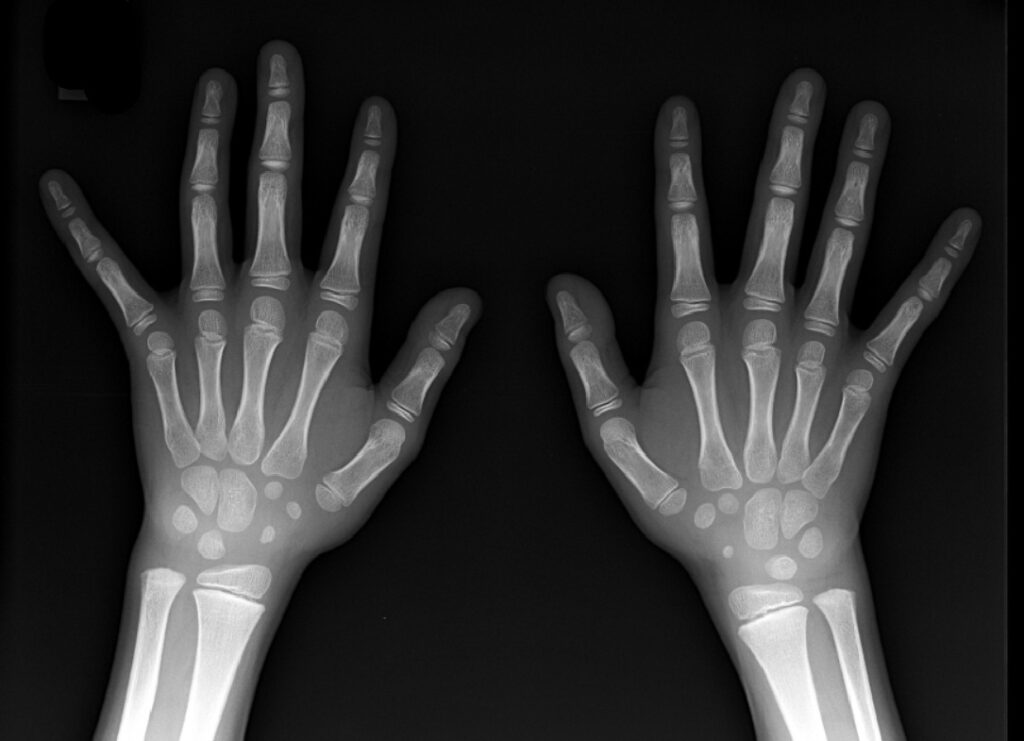

A Radiologia Convencional agora é digital ! Isso implica muitas vezes na facilitação dos trabalhos com equipamentos mais modernos, imagens mais claras e potencialmente mais diagnósticas, mas não esqueça da proteção radiológica. Ainda usamos raios X !!!